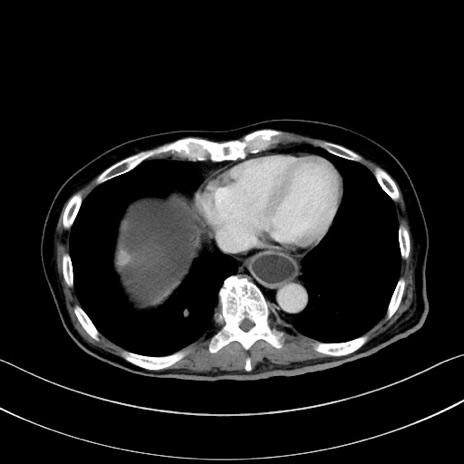

症例28(横断像)

【症例】60歳代男性

【主訴】嘔吐

【現病歴】胃癌にて胃全摘後。食思不振が悪化し、夜中に嘔吐することがある。

【既往歴】胃癌、胃全摘、脾摘、胆摘後

【データ】WBC 5900、CRP 10.56